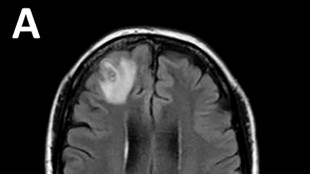

Un Franco-Canadien remporte un grand prix scientifique pour un traitement contre le cancer

Lorsque Michel Sadelain a commencé ses recherches pour programmer des cellules du système immunitaire à combattre le cancer, beaucoup de collègues sceptiques ont tenté de le décourager, jusqu'à sa propre mère, inquiète pour sa carrière.